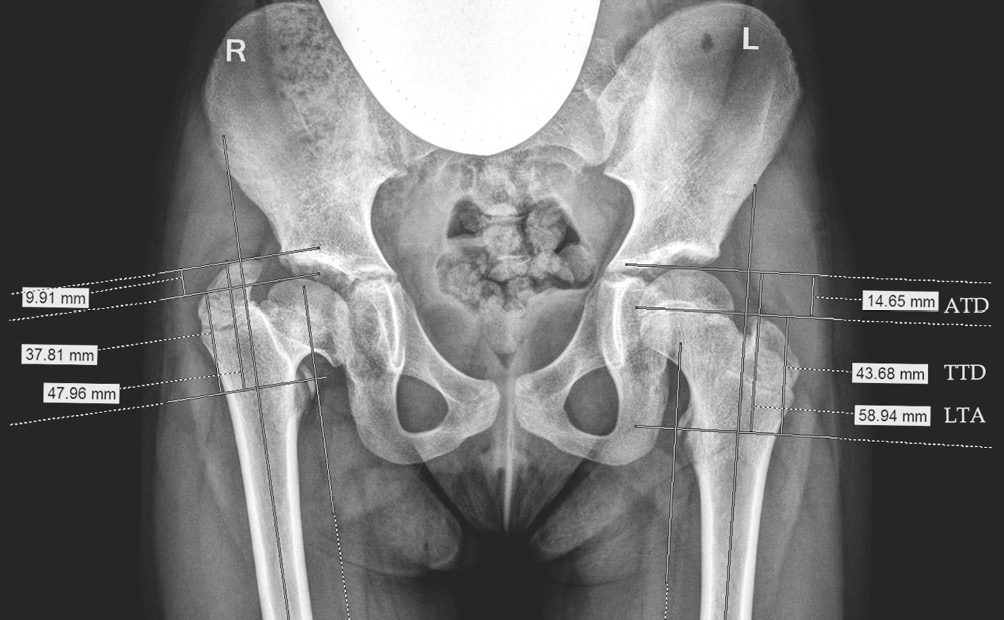

Несмотря на полиэтиологичность представленных групп пациентов, у всех обследуемых детей рентгенологические нарушения были сходными — показатель отношения верхушки большого вертела к центру головки бедренной кости принимал патологические значения. В рамках данной работы мы подробнее останавливаемся на индексах, характеризующих изменения роста большого вертела относительно головки и шейки бедра. Для уточнения динамики изменений рентгенологических показателей проксимального отдела бедренной кости были проанализированы цифровые рентгенограммы 56 обследованных больных (112 суставов), выполненных с соблюдением правильного масштабирования, в том числе при помощи калибровочного объекта для получения корректных данных (рис. 6).

Рис. 6. Пример рентгенометрического анализа показателей, характеризующих изменения положения большого вертела относительно головки и шейки бедра. ATD — артикуло-трохантерная дистанция; TTD — межвертельное расстояние; LTA — расстояние от малого вертела до верхнего полюса головки бедра

Во II группе детей школьного возраста с пораженным тазобедренным суставом наблюдалась та же динамика по изучаемым показателям, однако рентгенологические изменения были более выраженными, особенно у детей старше 10 лет. Значения ATD составили (–)2,3 ± 9,2 мм; TTD — 45,7 ± 11,7 мм; LTA — 54,0 ± 9,5 мм (см. рис. 8, табл. 1).

В нормальном тазобедренном суставе численно большим показателем из перечисленных является LTA. При выраженной гипертрофии большого вертела величина ATD принимала отрицательные значения, а показатель TTD становился больше LTA. Как видно на графике, это было характерно для подростков при сформировавшейся к окончанию роста деформации (рис. 9).

Рис. 9. Рентгенограмма пациента Б., 13 лет. Диагноз: «Состояние после консервативного лечения врожденного подвывиха бедра с двух сторон — последствия асептического некроза головки и шейки бедренной кости, высокое положение большого вертела». Вертельно-тазовый конфликт обусловлен выраженными анатомическими нарушениями, которые сопровождаются характерной клинической картиной и болевым синдромом